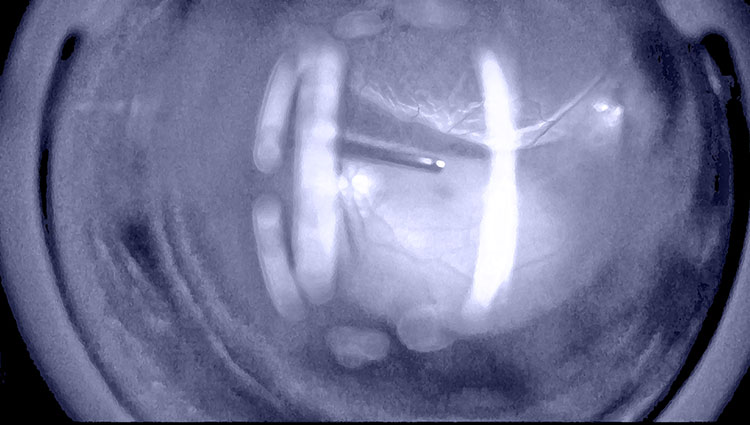

硝子体手術の適応疾患としては、高度な手技が求められるものの比較的短時間で済む黄斑前膜や黄斑円孔などの黄斑疾患をはじめ、難易度が高く所要時間も長くなることが多い裂孔原生網膜剥離、増殖糖尿病網膜症、増殖硝子体網膜症など、多岐に渡ります。

近年の手術機器の進歩は硝子体手術の領域においても目を見張るものがあります。現在では眼球内への器具の出入りは25G(ゲージ)や27G(ゲージ)といった非常に細い規格の出入り口を介するようになり、手術そのものが非常に眼に優しいものとなりました。また安全性もより高まっています。

なお、黄斑円孔網膜剥離には長期滞留ガス(C3F8)の注入を、難治性網膜剥離に対してはシリコーンオイル注入までを可能とし、また眼内をしっかりと明るく照らすツインシャンデリア照明や広範囲に剥離し浮き上がった網膜を術中にしっかり押さえつけるためのパーフルオロカーボンなど、術中に使用するアクセサリー類や手術補助薬剤などの準備にも抜かりなきよう心がけることで、手術成績のさらなる向上に努めております。